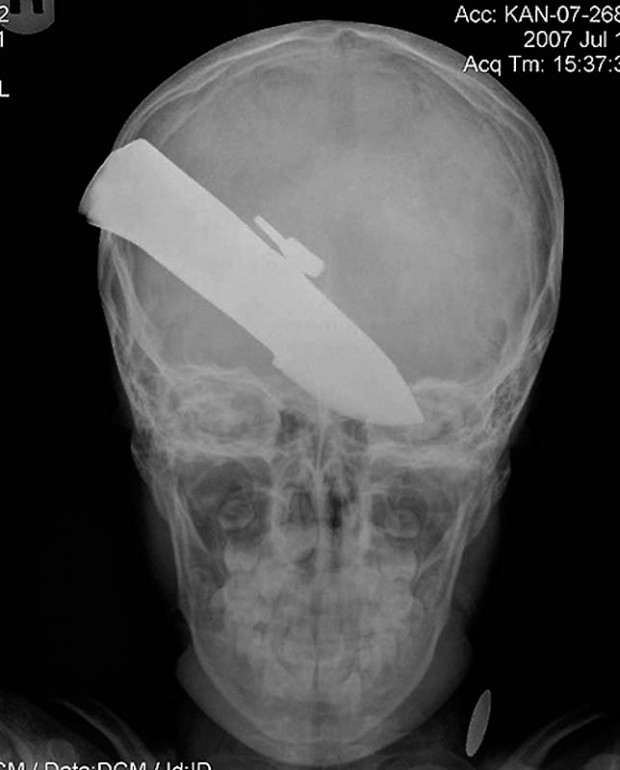

18. 12-сантиметровый нож в черепе подростка.